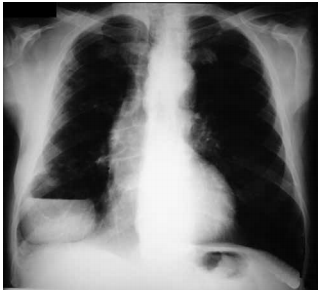

Paciente de 66 anos, sexo masculino, chega ao ambulatório relatando quadro de tosse, expectoração amarelada e febre (39 ºC) há 2 dias, acompanhada de dor torácica. Ele também refere etilismo e tem dentes em mal estado de conservação. Ele satura 91% em ar ambiente e a frequência respiratória encontra-se em 28 ipm. A seguir o raio X de tórax.

enunciado 601331-1